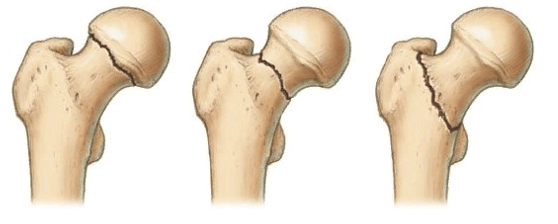

Локализация наиболее распространенных переломов.

По данным научно-медицинских источников в структуре всех нарушений ортопедического характера порядка 1,3% приходится на врожденные анатомические аномалии бедра. Дисплазии тазобедренного сустава диагностируются практически у каждого третьего новорожденного, в 80% они определяются у девочек.

Корригирующая остеотомия ТБС

Основная задача - откорректировать угол осевой деформации кости на уровне наибольшего искривления после правильного расчета патологического отклонения. Распространенными примерами, когда делают угловую коррекцию, служат анкилозированные суставы, рахитические искривления, неправильно сросшиеся костные переломы, другие посттравматические деформации, артрозы. Предпочтение чаще отдается межвертельному угловидному, косому и клиновидному способам пересечения с внутренней металлофиксацией выровненной зоны.